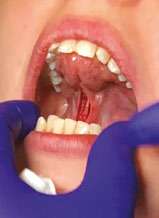

The laser nozzle was held 1-2 mm away from the target tissue (Figure 3B) and moved in a steady hand speed for controlled depth of incision motion. The myofunctional therapist was present throughout the entire procedure. In the course of the procedure, the dentist stopped several times, while the therapist assessed the remaining tension and the tongue mobility. First, after the dentist removed the most apparent, superficial fascial restriction, the myofunctional therapist measured the basic range of motion (ROM), palpated the tongue, using gentle experienced touch and trying to locate the presence of tightness or restriction. The patient was asked to lift, extend the tongue, and put it in the “suction-cup” position. The patient was already able to protrude and elevate her tongue better, but there was still tension and the dentist proceeded with a deeper release. At this point, no cutting was done; instead, blunt dissection was used to divide deep fascia – this technique helps the natural release, almost “melting”, of fascia. After that, the patient reported the sensation of the front neck tension alleviation. By the end of the procedure, the myofunctional therapist felt a release of the tension in the mid-portion of the tongue, where a big knot had been detected during preoperative examination. Finally, the last bit of tension detected by the myofunctional therapist was addressed by extending the incision vertically, upward, with the laser (Figure 3E).

The dentist pointed out that if she decided to not suture the surgical site, she would have ablated mucosa laterally (and created more of a diamond shape, as she does in infants and toddlers). For this patient, however, the frenum release was more linear (vertical) (Figures 3D and 3F) and sutures have been placed to facilitate healing without the need to worry about postoperative wound management to prevent return of ankyloglossia and begin OMT 72 hours postoperatively (Figure 3H).